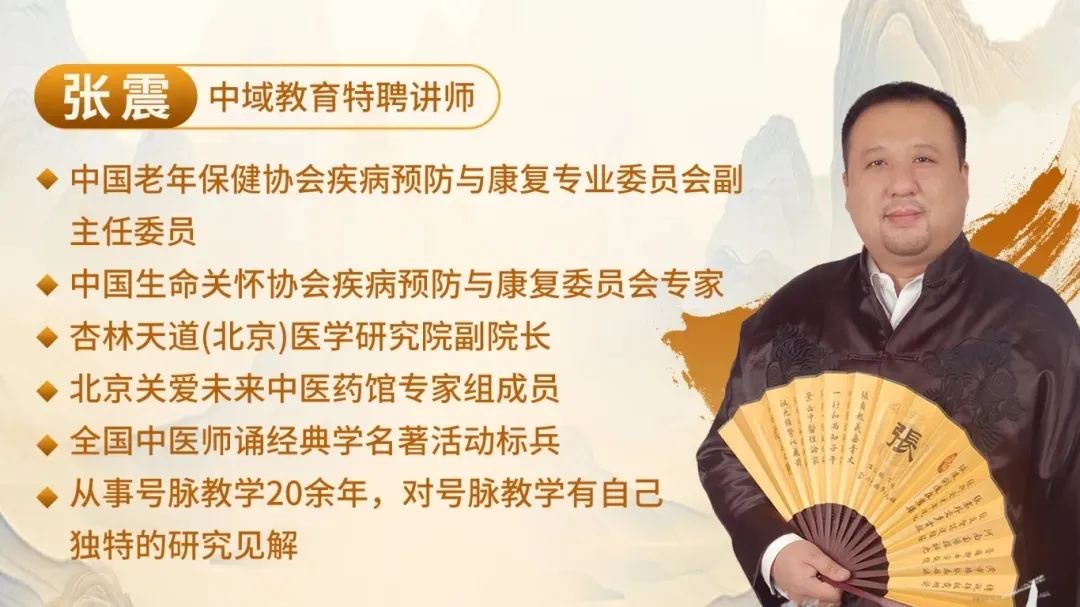

原来,他拜北京一位名叫张震的胖中医为师,学习了几乎失传的中医秘术——夺心术。

张震出身中医世家,“人人会中医、人人能自治”,是他祖辈世世代代在钻研和传承的事情。

张震从医三十余年,将中医学习的三大高山:理、法、方,全面梳理、逐一击破。